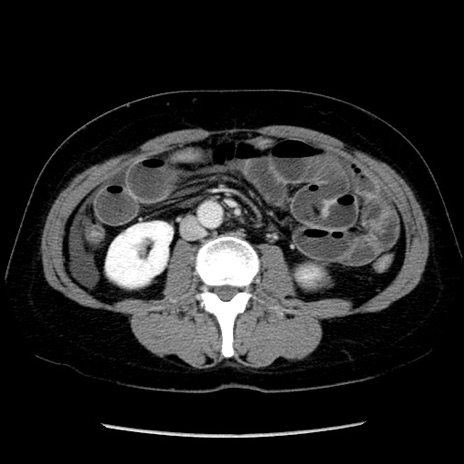

症例6(横断像)

【症例】50歳代女性

【主訴】下腹部痛

【現病歴】本日朝より下痢2回あり。 昼食を食べた後、嘔吐3回、下腹部痛認め、症状軽快せず、当院救急搬送。

最終食事:本日昼(生ものなし)。 昨日の夜、刺身を食ぺたとのこと。周囲に同様の症状の者なし。普段、排便は毎日あるとのこと。

【既往歴】卵巣癌術後(8年前に当院で卵巣摘出)

【身体所見】 意識清明、腹部:平坦、腸蠕動音→、やや硬、下腹部自発痛・圧痛あり、反跳痛あり、筋性防御なし。

【データ】WBC 16000、CRP 0.01